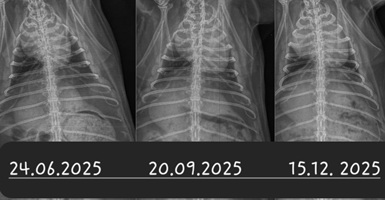

Ein Kaninchen mit Atembeschwerden oder den beschriebenen Augenveränderungen sollte zunächst geröngt werden. Hierdurch lassen sich Verschattungen im Brustkorb schnell und einfach erkennen und es muss anschließend nur noch ermittelt werden, ob es sich dabei um einen Tumor oder eine (reine) Herzerkrankung handelt. Letztere kann zu einem vergrößerten Herzen oder einem Erguss führen, was per Röntgendiagnostik nicht immer von einem Tumor zu unterscheiden ist.

Besteht eine entsprechende Verschattung, ist ein Herzultraschall angezeigt. Dabei können das Gewebe und die Herzfunktion eindeutig beurteilt werden. Dies ist auch deshalb von Bedeutung, da die Herzfunktion durch einen benachbarten Tumor beeinträchtigt werden kann. In diesem Fall muss das sekundäre Herzproblem in die Tumortherapie mit einbezogen werden.